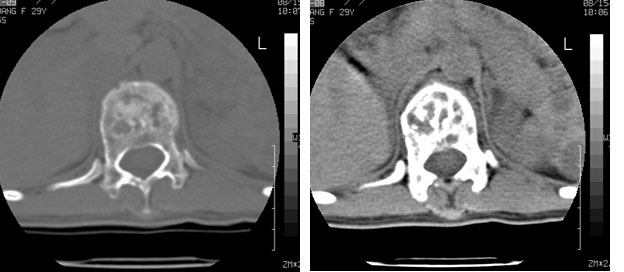

标题: CT10087:女,29岁,多发肿瘤样病变。

车祸致t12压缩性骨折,行ct扫描意外发现椎体多发肿瘤样病变,建议加拍骨盆平片,患者平常无症状。

考虑多发骨髓瘤可能性大。(骨松质内弥漫性分布,边缘清晰的溶骨性破坏,无硬化。睥脏增大,其内有多个圆形底密度影。淋巴瘤不除。

椎体多发性溶骨性破坏,部分融合,椎旁无软组织肿块、椎间隙正常,t12 压缩,脾脏增大,其内示多发低密度影,首先考虑多发性骨髓瘤。病人较年轻,平素无异常,转移瘤可能性小。